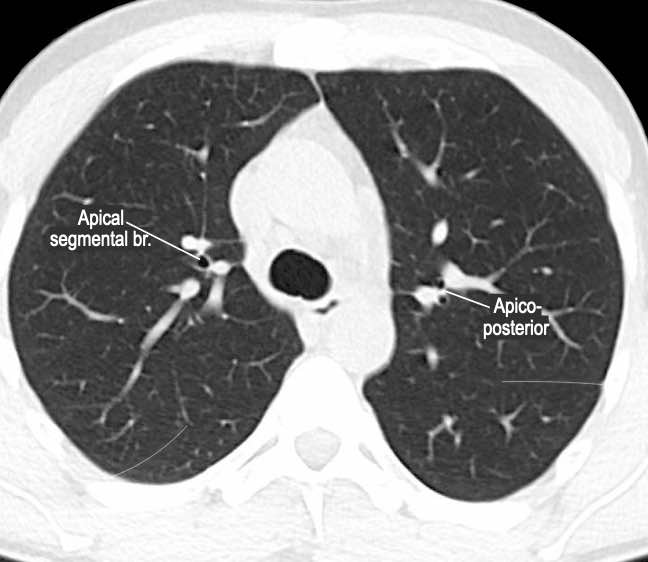

Phế quản trên CT

Cuộn qua các hình ảnh để quan sát khí quản phân chia thành phế quản chính phải và trái, sau đó tiếp tục phân chia thành các phế quản thùy và phế quản phân thùy.